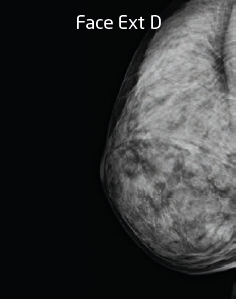

LES PROGRÈS DE 10 ANS DE MAMMOGRAPHIE ET D’ECHOTOMOGRAPHIE

Les progrès récents, en imagerie tant mammographique qu’échotomographique, sont extraordinaires et ont modifié profondément l’approche diagnostique. Rappelons que l’image n’est pas l’objet et que le diagnostic de cancer est histologique. Les premières images mammographiques ont été pratiquées en 1913 à Berlin par le Professeur Albert SALOMON, amélioration extraordinaire en 1944 en Amérique du Sud par…